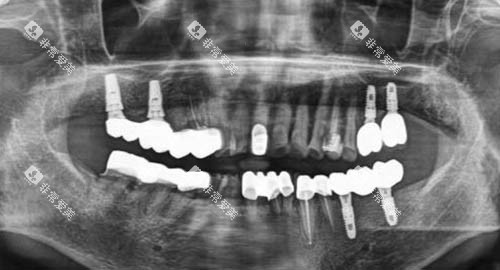

牙周病是成年人牙齿脱落主因,种植体周围炎则威胁种植牙寿命,二者根源均为细菌生物膜。

传统治疗难以穿透生物膜,易损伤正常组织,且复发率高。

冀城口腔采用的光动力技术,是国内外比较靠前的 “定向杀菌” 方案:将光敏剂涂抹病变部位,其优先被有害细菌吸收,再用特定波长光照射促活,产生活性氧精密杀菌,不损伤正常组织。

该技术优势显著:其一,不痛舒适,无需手术,患者轻松完成治疗;其二,较高的效率杀菌,破坏生物膜,控制炎症、促进愈合,延长种植牙寿命 5-10 年;其三,靠谱无耐药性,物理杀菌无需抗生素,对老人、儿童友好。